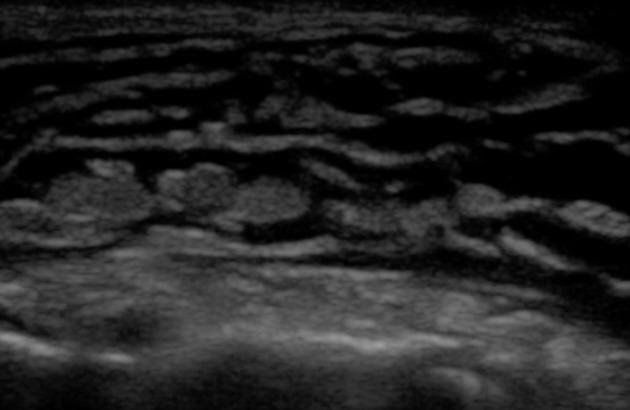

Sự tích tụ dần dần của phù nề trong mô dưới da tạo hình ảnh các dải dạng đường trống âm có phân nhánh tạo nên hình ảnh các thùy hay còn gọi là hình "đá cuội"(cobble-stone).

+ Hình ảnh này cũng có thể gặp ở các trạng thái phù nề khác

+ Sự hiện diện của da dày và phản âm bất thường bên trên sẽ nghiêng về viêm mô tế bào hơn là phù nề

+ Các dải dạng đường trống âm do dịch nằm sâu trong lớp mô dưới da ám chỉ phù bạch mạch.